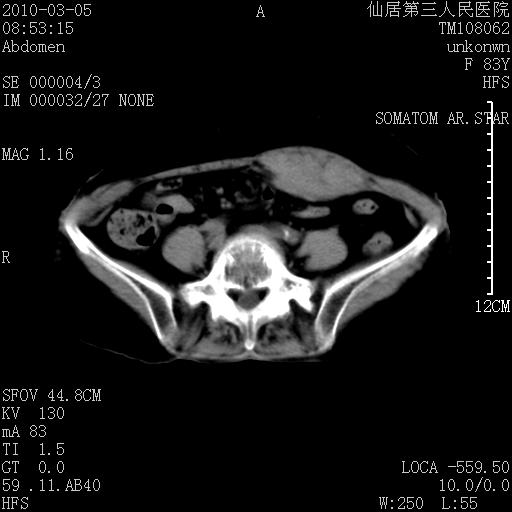

标题: CT24879:腹直肌病变。在线等。 [打印本页]

标题: CT24879:腹直肌病变。在线等。

女性,83y,腹痛一周。

考虑:左侧腹直肌神经纤维瘤可能

神经纤维瘤—伴有出血?

有无外伤,血肿或韧带样瘤

考虑左侧腹直肌血肿,肿瘤性病变待排。

增强看看,mfh可能性大,次之可考虑血肿、bfh、转移瘤、神经纤维瘤、侵袭性韧带样纤维瘤等。肝内钙化灶,右肾结石。

血肿,纤维瘤,子宫内膜异位都有可能。